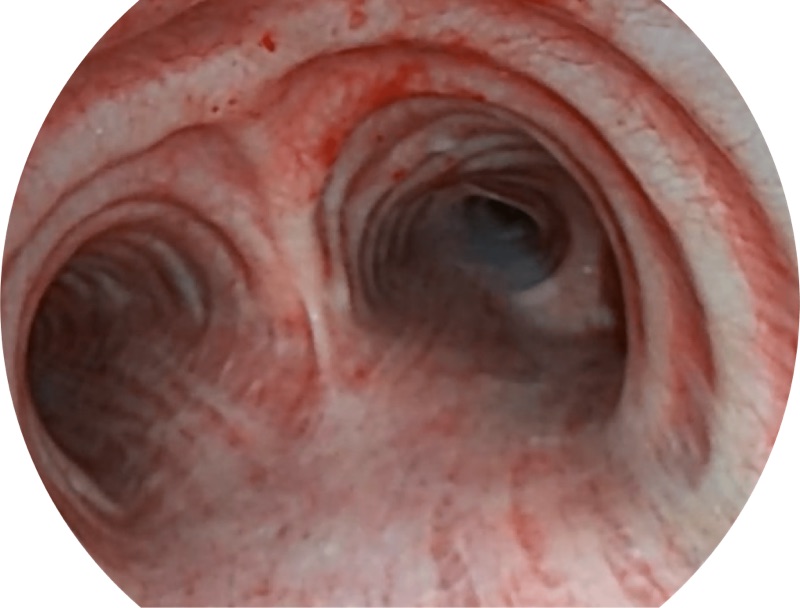

帮助医生更加清晰地观察气管表面病灶

EB-5H20具有4.9mm外径及2.0mm钳道提升对外围支气管检查能力

VIST